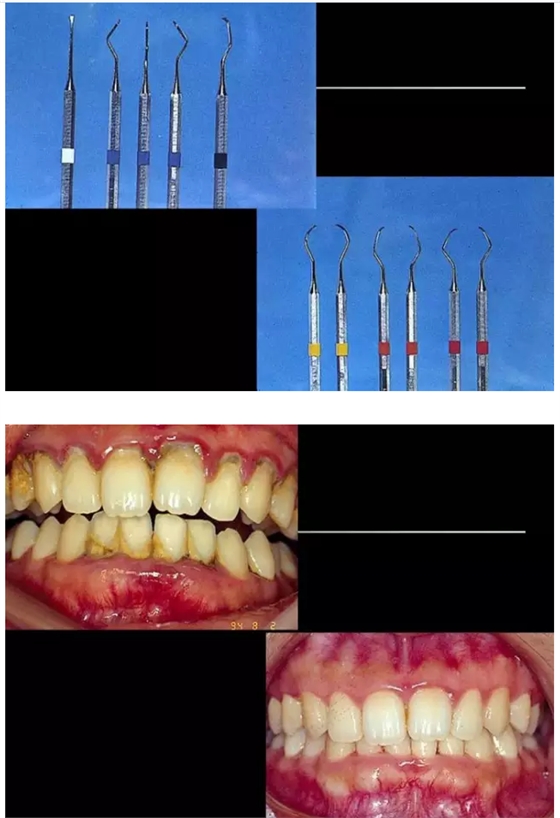

【牙科知識(shí)】牙周病相關(guān)手術(shù)圖解,非醫(yī)學(xué)專業(yè)勿點(diǎn)